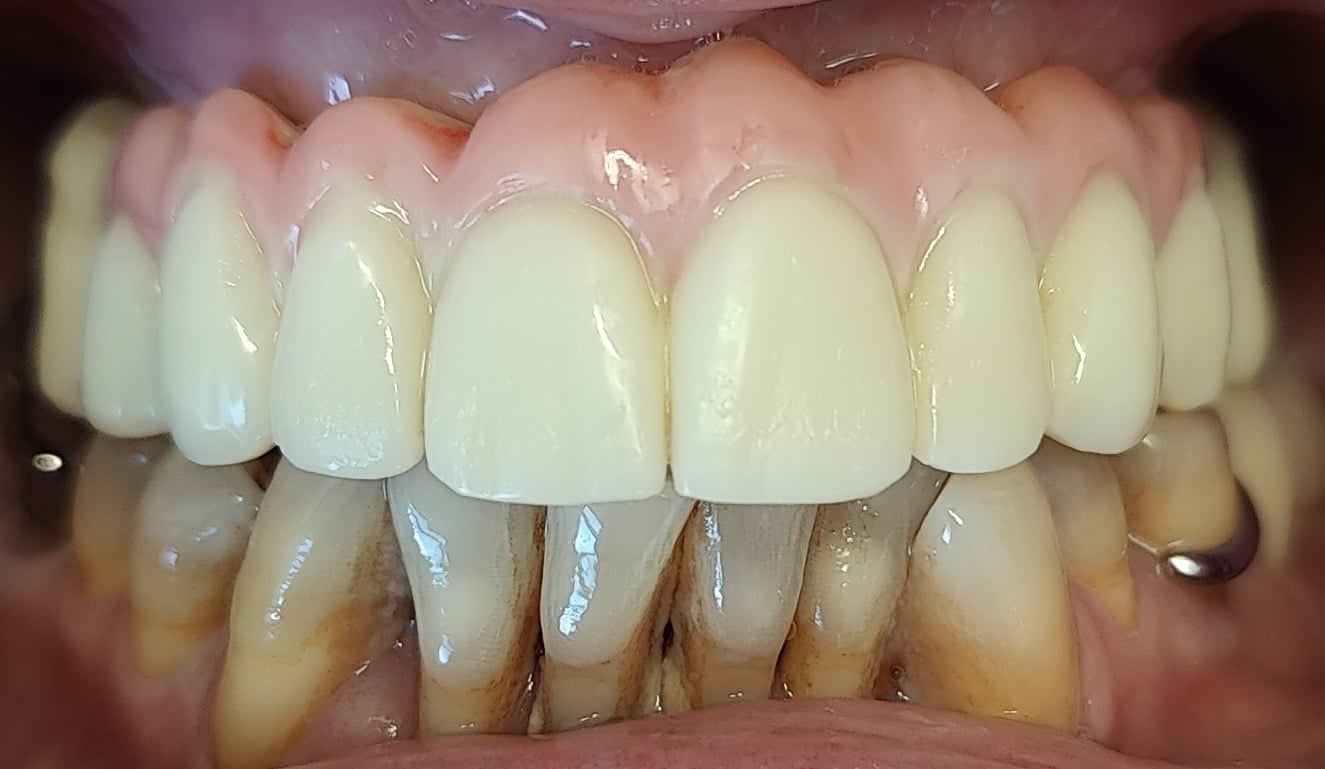

Bridge provisoire en place avec un rendu esthétique satisfaisant :

Détail de la fausse gencive du bridge provisoire en bouche :

Aspects esthétiques à 4 mois :